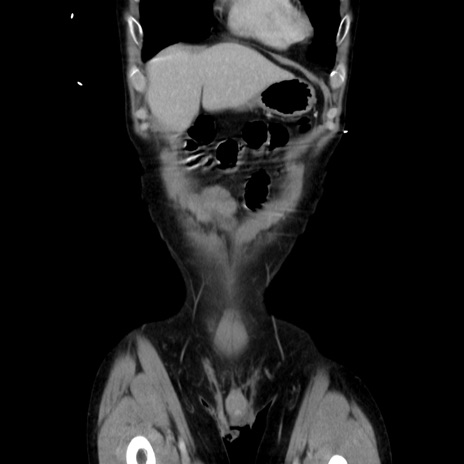

症例37(冠状断像)

【症例】40歳代 男性

【主訴】腹痛

【現病歴】4時間ほど前に電車に乗車中に臍部上より腹痛出現。徐々に増悪し起立困難となり、救急外来受診。生ものは数日食べていない。今朝お雑煮を食べた。

【身体所見】BT 36.8℃、BP 117/84mmHg、HR 91/min、SpO2 97%、苦悶様、腹部:臍上部広範囲圧痛あり、反跳痛±

【データ】WBC 8100、CRP 0.03